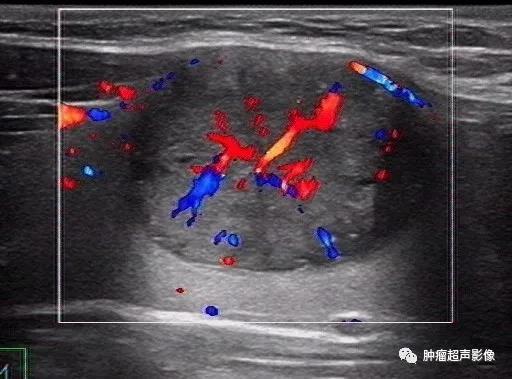

彩色多普勒血流信号在甲状腺良恶性结节的鉴别诊断中并无多大价值,各个版本TI-RADS分类未采纳彩色多普勒血流(甲状腺KWAKTI-RA...